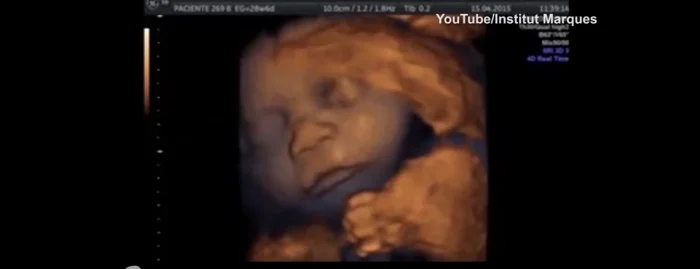

2. Чудо-ребёнок

В 1989 году на свет появился здоровый ребенок, несмотря на то, что его мать перенесла инсульт и была признана мёртвой из-за смерти мозга. Он провёл в утробе женщины, подключённой к системе жизнеобеспечения, 107 дней.